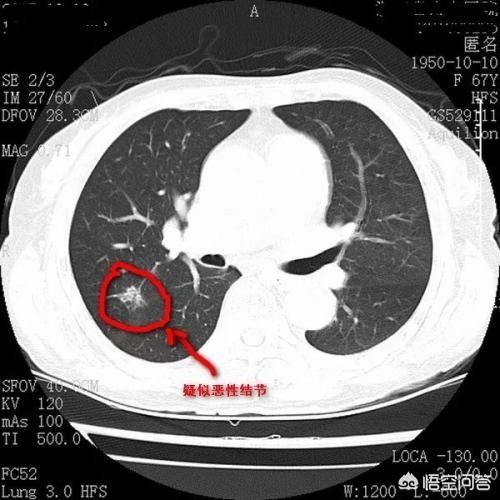

矢印は結節を指しているが、2016年3月に発見されたときは約0.5cmと非常に小さかったが、今では定期検診でこのように非常に多くの結節が見つかっている。画像で良性か悪性かを判断する方法はなく、検討するという選択肢しかなく、検討と経過観察も最良の手段である。

7ヵ月後、2016年10月の2回目の経過観察では、この結節がより大きく、丸みを帯びていることが明らかになった。経過観察時の結節の拡大は悪性腫瘍の可能性を警告するものであったが、この患者はそれでも手術を選択しなかった。

肺の小さな悪性結節はしばしば典型的な悪性腫瘍の徴候を示し、結節内部の密度はしばしば不均一で、初期の結節ではすりガラス状になったり、すりガラス状の密度が混在するものもあり、結節の一部に小さな空洞が見られることもある。悪性結節は栄養補給のために大量の血液を必要とするため、辺縁部にはしばしば短いバリが浸潤しているのが見られ、血管集塊と呼ばれる小さな血管の集合体が小結節の小血管に近接して見られることもあるため、辺縁部はさらに典型的である。

肺に上記のような徴候のある疑わしい結節を見つけたら、特に混合バリ結節に高い注意を払うべきで、これは時間内に治療するか、あるいは綿密に経過観察すべきです。また、よく地肌結節と呼ばれるものがありますが、地肌結節は密度と縁、また経過観察時間とプログラムの直径の大きさに基づいて、炎症性結節と考えられる場合は、抗炎症後に結節の変化の吸収と縮小があるかどうかを観察して比較検討する必要があります。肺に小さな結節が見つかった場合は、神経質にならず、結節の特異的な症状に応じて、他の臨床検査を行い、検査や経過観察に進む必要があるかどうかを判断する。